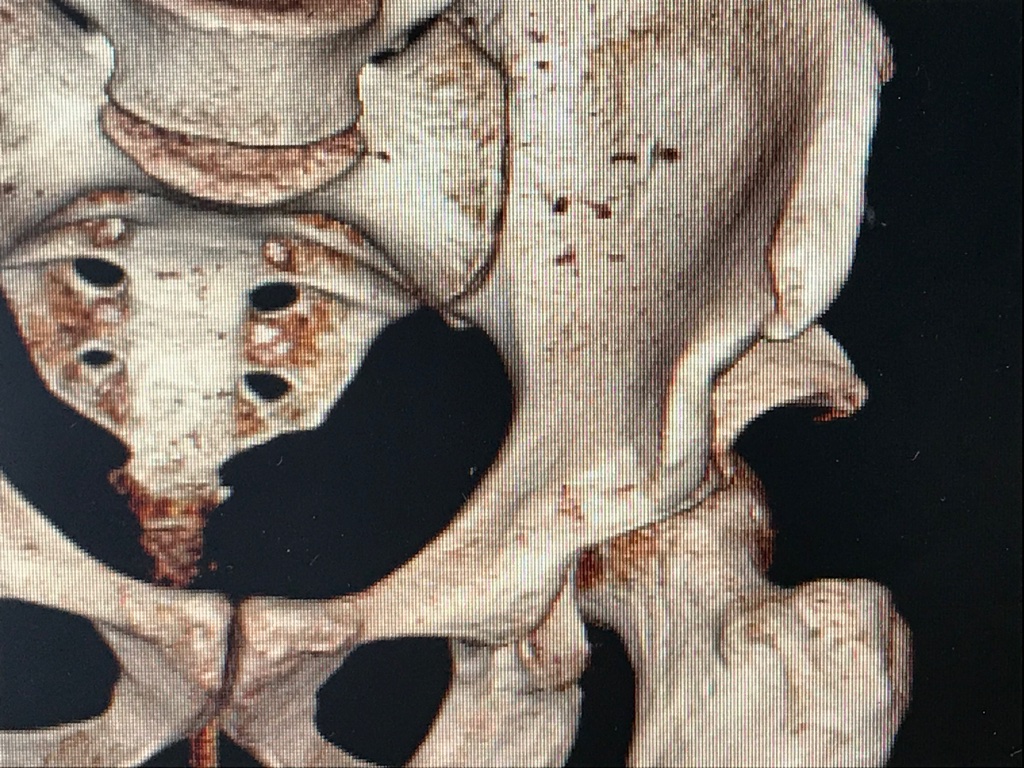

- Una frattura di bacino in un Calatino:

Postoperatorio